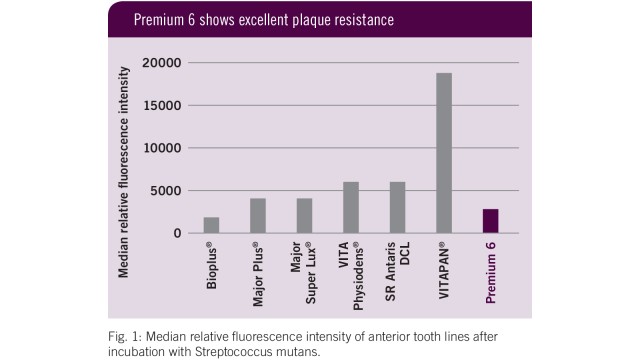

Flexecure® - per la massima resistenza all’abrasione e alla frattura

- Il nostro materiale brevettato è composto da microriempitivi combinati con nano particelle visco-elastiche.

- Il risultato: elevata resistenza all’abrasione, opalescenza naturale, qualità della superficie abbinata ad una straordinaria resistenza alla frattura e quindi una eccezionale longevità del dente.

- 100% di stabilità del colore